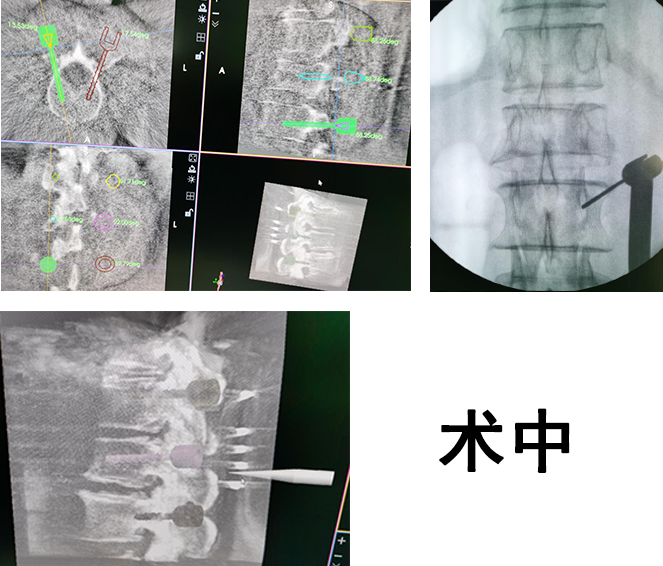

手术中,先由C型臂对患者进行三维影像扫描,图像被同步传输至骨科机器人系统。手术医生在导航系统屏幕上设计好钉道,机器人的机械臂将手术工具精确定位到手术位置,套筒指向目的钉道的进钉点,从而实现螺钉的精准安全植入。随后,手术小组对右桡骨骨折进行处理,复位骨折端,克氏针固定,安装桡骨远端骨折外固定架,打入骨钉,确定内固定位置良好。手术很成功。

“有了‘天玑’机器人,相当于给骨科医生装上了‘透视眼’和‘第三只手’,大大提高了手术精准度,降低了手术风险。”孟医生说,传统的脊柱手术,由于手术位置深、且毗邻重要神经和血管,因此风险非常高,手术切口大、出血量大,手术时间也较长,术后还经常伴有并发症。采用骨科机器人后,能够有效解决骨科手术视野差、精准难、置钉不稳定的难题。“天玑”机器人拥有强大的光学追踪系统和机械臂,追踪系统可以进行三维透视扫描,能看到人眼看不到的地方,还可以实时监控手术每一个环节;机械臂运动灵活、操作稳定,精准度可达到0.8毫米。

“以今天的手术为例,如果采用传统手术,需要切开近20厘米的切口,有了‘天玑’机器人的辅助,只需在患者腰椎切开几个不到1厘米的小切口,就可以进行操作,基本不造成肌肉软组织的损伤,且患者的骨折复位效果理想、固定稳定,真正实现了微创、精准。”孟医生说。